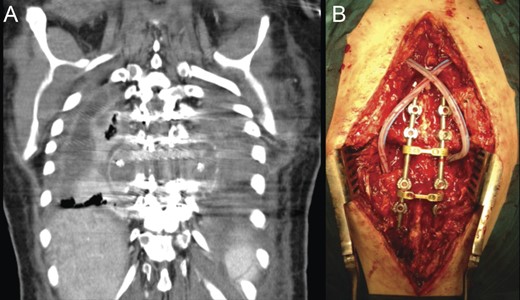

Due to the advanced stage of the lesion, with associated instability that could result in major neurologic deficits in a short time period, a total en bloc spondylectomy of T8 by a posterior-only approach was performed (Fig. 2). The operation followed the technique proposed by Tomita et al. and was complemented with anterior-column reconstruction with a titanium mesh filled with structural allograft, as well as pedicle screw instrumentation, from T6 to T10 (Fig. 3). During the procedure, the eighth dorsal nerve routes were sacrificed.

Intraoperative photographs; after total en bloc spondylectomy (A), anterior-column reconstruction was accomplished with placement of a titanium cage with structural allograft (B) and was complemented with pedicle screw-rod fixation (C). (D) Resected vertebra.